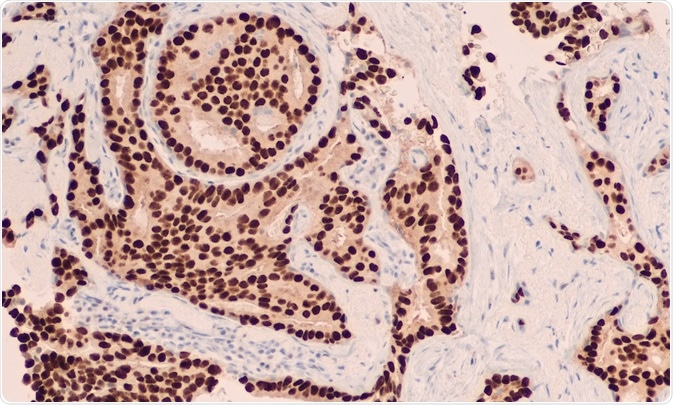

Immunohistochemistry (IHC) is an imaging technique to visualize antigens in cells. Labeled antibodies bind to target antigens in the cell to image the distribution and localization of specific proteins of interest.

The stained samples can be imaged by employing light or fluorescence microscopy. Confocal microscopy can be applied to certain antibody detection methods, and will yield greater detail. In the event of large data sets, high content screening analysis can be used to quickly quantify levels of cellular components and compare data from several samples.